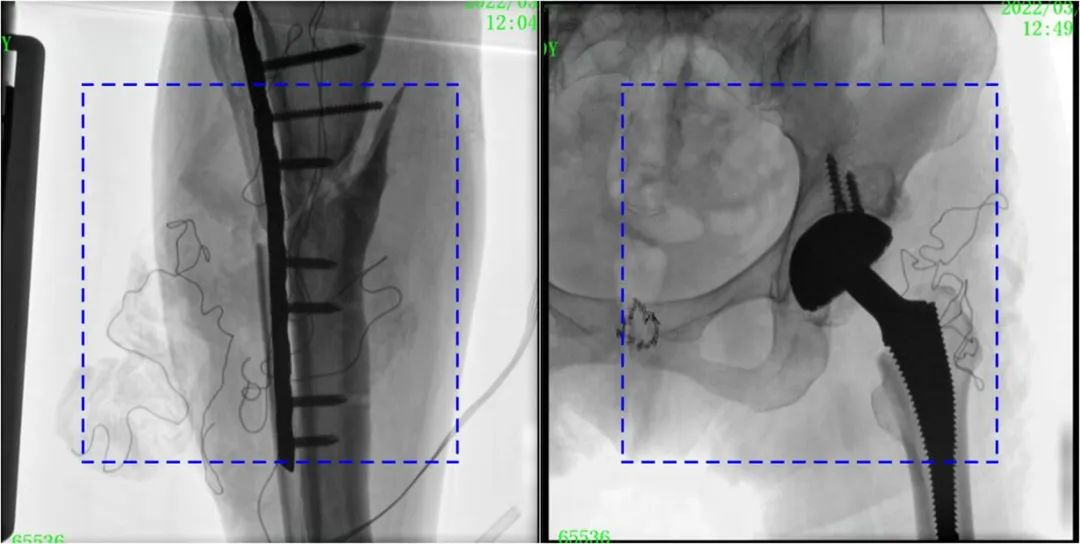

與傳統(tǒng)的21CM×21CM成像尺寸相比,普愛醫(yī)療大平板一體式C形臂具有30CM×30CM更大成像尺寸,能夠一次成像5.5節(jié)椎體,呈現(xiàn)更全面的影像信息,即便是手術(shù)經(jīng)驗(yàn)不豐富的年輕醫(yī)生也能通過圖像迅速判斷椎體節(jié)段、定位手術(shù)部位,避免因?yàn)橐曇安蛔愣斐傻亩啻味ㄎ?、反?fù)曝光,提高效率的同時(shí)避免過量攝入輻射。

普愛醫(yī)療大平板一體式C形臂圖像與傳統(tǒng)圖像對(duì)比(藍(lán)色虛線內(nèi)為傳統(tǒng)21CM×21CM平板的成像區(qū)域)